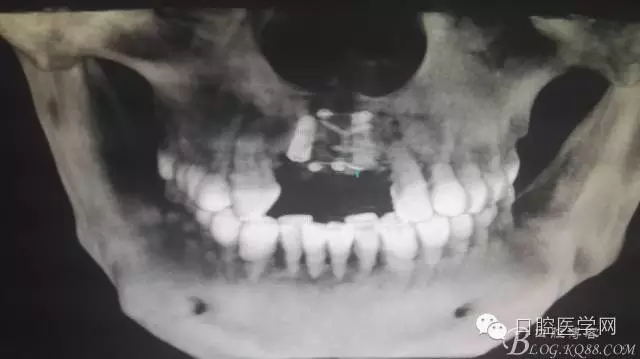

植入種植體左側3510,右側4010,植骨Bioss,蓋膜Cytoplast。骨膜減張垂直褥式縫合加間斷縫合。

半年后...

后期的修復工作由之前的轉診醫(yī)生后續(xù)處理,由于GBR過程骨膜減張導致角化牙齦不足3mm,建議角化牙齦移植改變其更好的牙齦生物型。